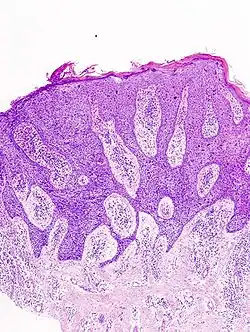

In situ disease

Bowen's disease is essentially equivalent to and used interchangeably with cSCC in situ, when not having invaded through the basement membrane.[12] Depending on source, it is classified as precancerous[13] or cSCC in situ (technically cancerous but non-invasive).[48][49] In cSCC in situ (Bowen's disease), atypical squamous cells proliferate through the whole thickness of the epidermis.[12] The entire tumor is confined to the epidermis and does not invade into the dermis.[12] The cells are often highly atypical under the microscope, and may look more unusual than the cells of some invasive squamous-cell carcinomas.[12]

-

cSCC in situ, high magnification, demonstrating an intact basement membrane.[12] -

cSCC in situ -